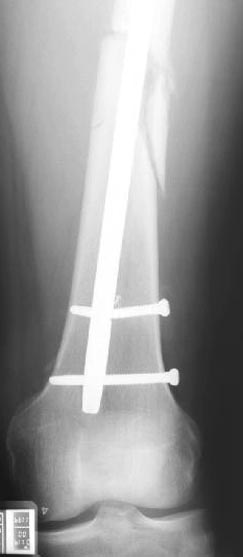

Снимки представлены: 1 мес; 3 мес; 1 год; 2 года, предоперационные и ротационная КТ грамма

Деформация:

Вальгус- 17 градусов

Рекурватум 5 градусов

Укорочение 2.5см

Ротационно 22 градусов внутренная

Смещение диафиза по поперечнику 75%